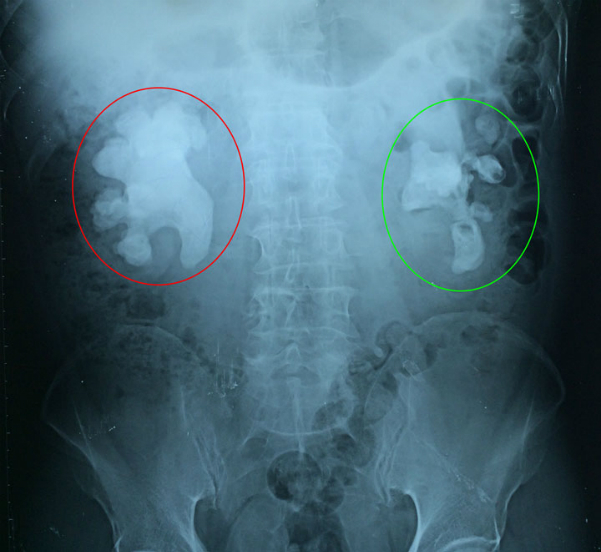

Đau bụng dữ dội, đi tiểu có lẫn máu, cụ ông ở Quảng Ninh, 71 tuổi đi cấp cứu vào bệnh viện. Sau khi chiếu soi thì bệnh viện phát hiện trong thận của cụ có một khối sỏi san hô lớn lạ kỳ.

Các bác sĩ Bệnh viện Việt Nam - Thụy Điển Uông Bí kết hợp với bác sĩ Bệnh viện Việt Đức vừa tiến hành phẫu thuật thành công lấy bỏ khối sỏi san hô kích thước 6 x 9 cm ra khỏi thận bên phải cho cụ ông.

Theo các bác sĩ, đây là một trường hợp phức tạp khi sỏi san hô ở cả 2 bên, hiếm gặp. Sỏi to lấp đầy toàn bộ các nhóm đài bể thận. Nếu không điều trị sỏi sẽ tàn phá làm mất chức năng thận, gây ra những đợt nhiễm trùng thận tái đi tái lại, đôi khi nhiễm trùng nặng có thể gây nguy hiểm tính mạng của người bệnh.

Sau khoảng hai giờ phẫu thuật, các bác sĩ đã tiến hành phẫu thuật thành công lấy khối sỏi lớn này ra khỏi thận phải của người bệnh. Quá trình phẫu thuật khó khăn bởi khối sỏi có kích thước lớn và xù xì, nhiều ngạnh, chỉ cần một sơ suất nhỏ có thể khiến cho người bệnh bị cháy máu, thậm chí phải cắt bỏ thận...

Bệnh nhân sẽ được phẫu thuật lấy sỏi thận bên trái sau khi ổn định sức khoẻ. Ảnh: Bệnh viện cung cấp.

Hiện, sau phẫu thuật, sức khỏe người bệnh ổn định, dẫn lưu vùng mổ đã hết dịch, nước tiểu trong. Sau khi sức khỏe người bệnh ổn định sẽ được tiến hành phẫu thuật lấy bỏ khối sỏi san hô tại thận bên trái.